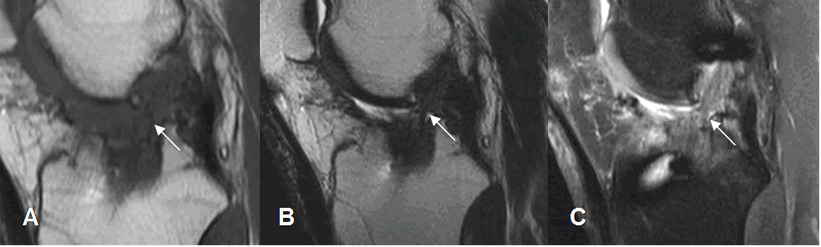

Fig 130. Túnel femoral normal.

A: Rx lateral y B: RM sagital en T1. Orientación normal del túnel femoral, en la parte posterior del cóndilo femoral.

Fig 131. Túnel femoral normal.

A: Rx AP y B: RM coronal en T1. Orientación normal del túnel femoral, dirigido hacia la 1, de las manecillas del reloj.

Fig 132. Mala orientación del túnel femoral.

A: Rx lateral. Túnel muy vertical y ocupando la parte media del cóndilo.